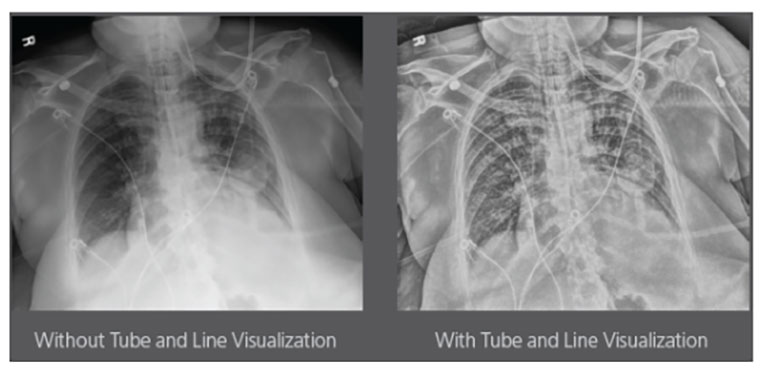

Carestream Introduces New Software Update to Boost Diagnostic Accuracy

Carestream today announced the latest update to its Image Suite V4 Software, MR 11: a series of enhancements to help improve customer confidence and increase diagnostic accuracy [...]